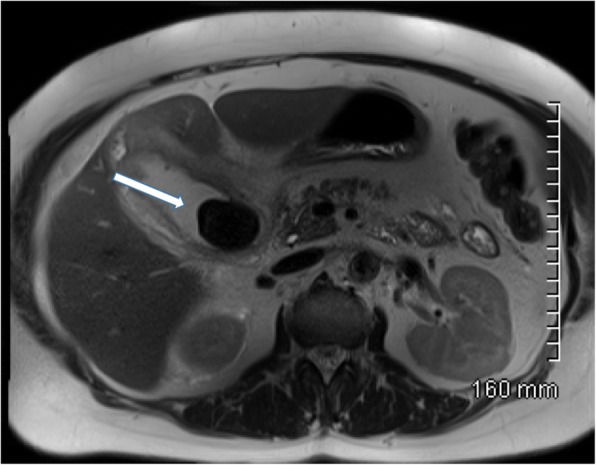

MRI is another very effective tool for diagnosing gallstones and associated pathological processes. Magnetic resonance cholangiopancreatography (MRCP) is typically performed using heavily T2-weighted sequences, supplemented by fat-saturated T1- and T2-weighted MRI, and with steady-state gradient-echo acquisitions. Heavily T2-weighted image sequences are particularly helpful in delineating ductal anatomy. Gallstones typically appear as low signal or signal void on T2-weighted imaging surrounded by T2 hyperintense bile [11] (Fig. 5). MRCP has largely replaced endoscopic retrograde cholangiopancreatography (ERCP) as the gold standard for diagnosing choledocholithiasis due to its high sensitivity of 90–94% and specificity of 95–99% without the use of ionising radiation or ERCP-related complications such as pancreatitis which can result in significant morbidity and even mortality [12, 13].

Fig. 5.

Axial T2-weighted MRI of the abdomen. There is a large gallstone within the gallbladder which is markedly hypointense relative to the surrounding hyperintense bile. The gallbladder wall is thickened with surrounding pericholecystic fluid consistent with acute cholecystitis